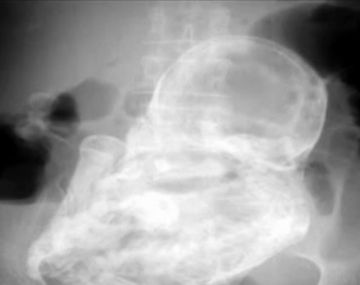

A los 82 años, descubrió que había estado embarazada por 40 años Los médicos descubrieron que los dolores abdominales que padecía eran provocados por la presencia de un feto que no se había desarrollado. Rarezas